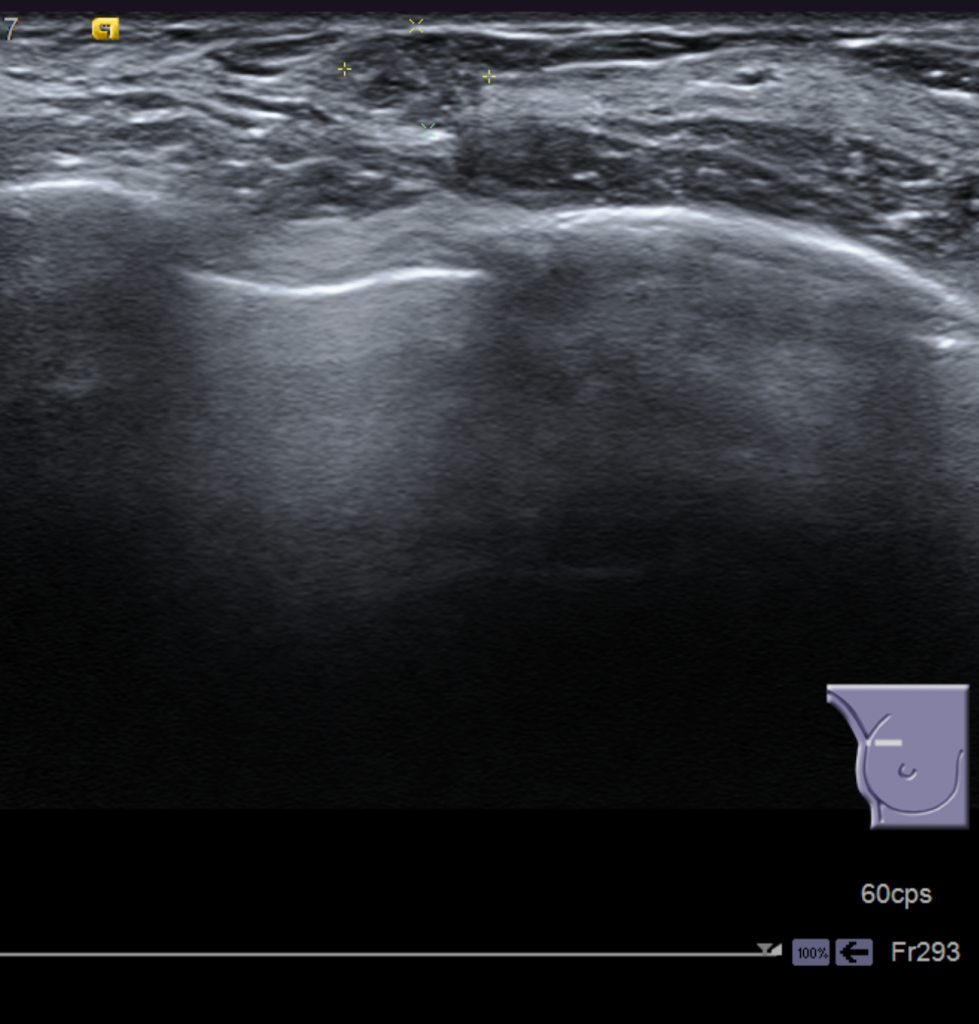

Como vemos en la imagen inferior, en la ecografía podemos encontrar un nódulo hipoecógenico, que no podíamos diferenciar en la mamografía, de bordes parcialmente definidos con microcalcificaciones puntiformes en su interior.

DIAGNÓSTICO FINAL: Carcinoma ductal ”in situ”.